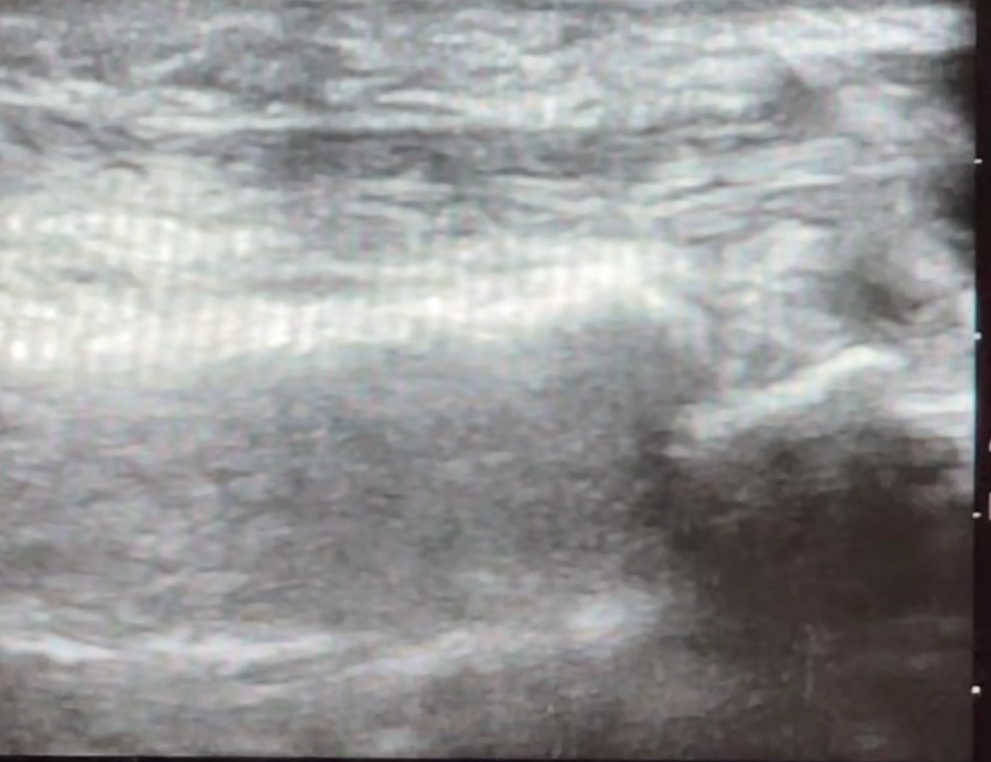

อัลตราซาวด์เป็นเทคโนโลยีที่ช่วยให้แพทย์มองเห็นตำแหน่งของพังผืดและเส้นเอ็นได้อย่างชัดเจน ทำให้สามารถระบุจุดที่เป็นปัญหาได้แม่นยำ เมื่อได้ตำแหน่งที่ต้องการแล้ว แพทย์จะใช้เข็มที่มีขนาดเล็กและบาง เพื่อทำการตัดพังผืดที่ก่อให้เกิดการติดขัดในบริเวณปลอกเอ็น

1. แพทย์จะใช้อัลตราซาวด์เพื่อตรวจหาตำแหน่งพังผืดที่หนาและก่อให้เกิดปัญหา

2. เมื่อพบตำแหน่งที่ชัดเจน แพทย์จะใช้เข็มขนาดเล็กเข้าทำการตัดพังผืดภายใต้การควบคุมของอัลตราซาวด์